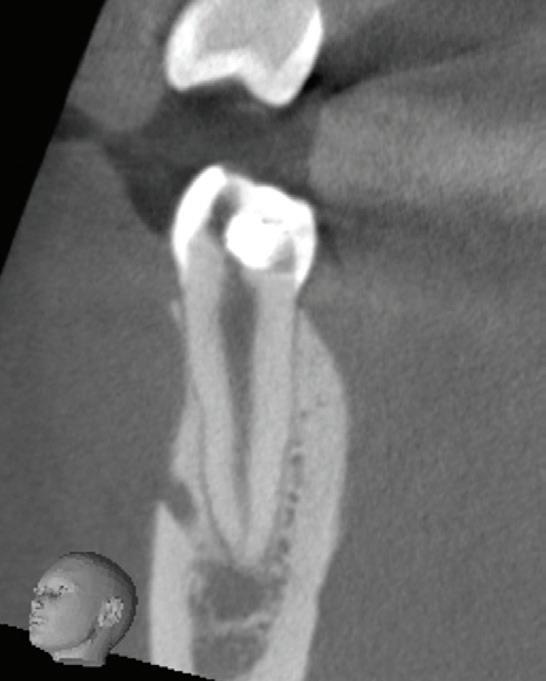

In the endodontic stage, conservative endodontic preparation and obturation with modern techniques are performed as they are for any tooth. All endodontic procedures are performed under an operating microscope to maximize visualization and illumination of the fracture line (Fig 1). The coronal portion of the newly placed gutta percha is removed 2 to 3 mm below the deepest extent of the crack in the affected canal to prepare for intraradicular barrier placement (Fig 2). Gutta percha is also removed 2 to 3 mm into the other noncracked canal orifices in the tooth to prepare for traditional orifice barriers. Microscopic transillumination with a fiber-optic light, in which an LED light probe is placed against buccal or lingual tissues overlying the roots, is utilized to illuminate the root and enhance visualization of the crack (Fig 3). A flowable resin-modified glassionomer or composite resin is then placed in this newly created void from the level of the gutta percha to the floor of the pulp chamber in all canal orifices (Fig 4). A composite resin core is then placed to permanently restore the endodontic access. If a temporary or permanent crown is not placed immediately after the endodontic procedures, the tooth is reduced

Periapical radiograph at the completion of the endodontic protocol. Resin-modified glass ionomer cement is placed as an intraradicular barrier in the distal canal, along the pulpal floor, and as an orifice barrier in the mesial canals.

Fig 1. Microscopic visualization of the radicular extension of the crack (arrows) entering the canal.

Fig 2. Gutta percha removed 2 mm apical to the terminus of the fracture (arrows).